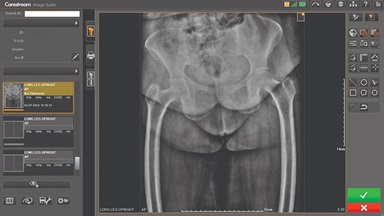

Carestream Focus HD 35/43 Retrofit Detectors Powered by Image Suite Software

High-Definition Detectors for Ultra-Detailed Imaging

Upgrading your imaging system to a solution designed for outstanding image quality is no longer out of reach — it's now easier, more affordable, and more effective than ever before.

Our Carestream Focus HD 35/43 Retrofit Detectors, powered by Image Suite Software, are an ideal solution to step up to full digital X-ray for customers who simply cannot compromise on image quality. It seamlessly integrates into existing setups, bringing the power of full digital X-ray with minimal disruption and maximum clarity, along with the following benefits: